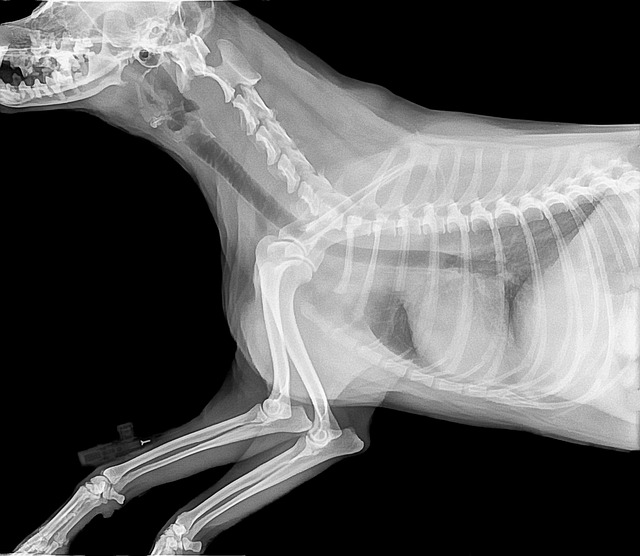

CT (or CAT) scans are advanced medical imaging techniques that allow veterinarians to obtain detailed cross-sectional images of a dog’s internal structures. These images are indispensable tools for diagnosing various medical conditions in dogs, from bone fractures to soft tissue injuries and certain types of cancer. Think of it as a high-resolution, three-dimensional snapshot of your pet’s insides, revealing intricate details that traditional X-rays or physical examinations might miss.

A Computed Tomography (CT) scan, often called a CAT scan, is a sophisticated medical imaging technique that plays a pivotal role in veterinary medicine. It uses a combination of X-rays and computer technology to generate cross-sectional, high-resolution images of a dog’s internal structures. Unlike traditional X-rays, which provide a two-dimensional view, CT scans create detailed three-dimensional images, offering a comprehensive look at a dog’s anatomy. These images are essential for diagnosing a range of medical conditions, making CT scans an invaluable tool in veterinary care.

While regular X-rays are useful for detecting bone fractures and specific soft tissue abnormalities, they lack the level of detail provided by CT scans. CT scans can reveal intricate structures, such as blood vessels, organs, and even subtle tissue abnormalities.

X-rays are a widely used diagnostic tool in veterinary medicine. They are relatively quick and cost-effective, making them suitable for initial evaluations of bone fractures, assessing the size and shape of organs, and detecting abnormalities such as foreign objects or lung conditions. However, X-rays provide two-dimensional images, which may lack the detail and precision of CT scans. In some cases, more complex situations may require additional imaging techniques for a comprehensive diagnosis.